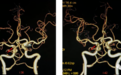

我们团队也有一些经验,有些案例来分享一下。我们在2019年初诊发现一个动脉瘤,这个动脉瘤是体检时发现的,是未破裂动脉瘤。患者女性,63岁。因为她是体检发现,所以我们做了人工AI的评估,从各方面分析提示动脉瘤破裂风险较高。换句话说,它不稳定且风险较高,尤其两年内进展的风险比较大,所以当时建议她做手术治疗。但是,因为病人首次发现,并且无症状,所以她当时考虑到手术风险就决定再观察,当时就签字观察了。6个月后再给她做CTA,在随访结果显示动脉瘤一年以后明显生长而且是一个多囊性的。然后我们将两次片子对比,建议患者积极手术治疗,最后这个病人积极做了手术治疗。确实在术中也看到了动脉瘤,并且发现新长了一个像子囊,比较红,很容易破裂。这与临床所见比较相符,所以我们就觉得这个只是一个辅助,可以帮助医生提高判断准确性。

王硕教授:过去这些平常说的动脉瘤的评分表,这些数据也是非常重要的。但是现在随着科技发展,我们现在把它纳入更多的一个深层的数据,就真正的血流方向。因为动脉瘤基本生长的位置都在血流改变的位置。所以我把这血流数据拿到了,再把动脉瘤管径,比如瘤颈和动脉瘤的直径,还有我们关键看动脉瘤瘤壁,就是动脉瘤瘤壁的厚度,有无强化,有无薄弱点。所以我们不光看到这个CTA,就是我们CT成像数据,我们可能还有血流数据,还有包括我们的高分辨核磁的数据,都要进行把它融合在一起,进行多维度、多角度的评估。当然数据越多,可能获得的判断越准确,所以可能还更需要更多的数据。